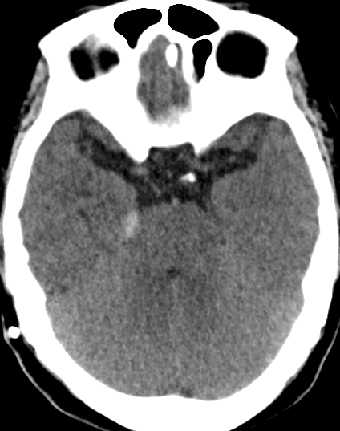

2013-8-8 CT

2013-8-7 脑室腹腔分流术,初压130